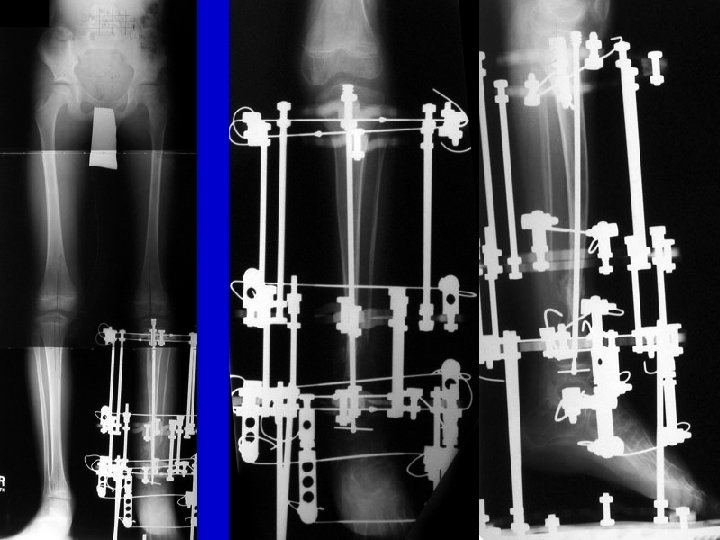

Type II Treatment Bone transport Acute shortening

CPT resection

acute shortening re-lengthening

bone transport healed

Re. Fx IM rod follow-up